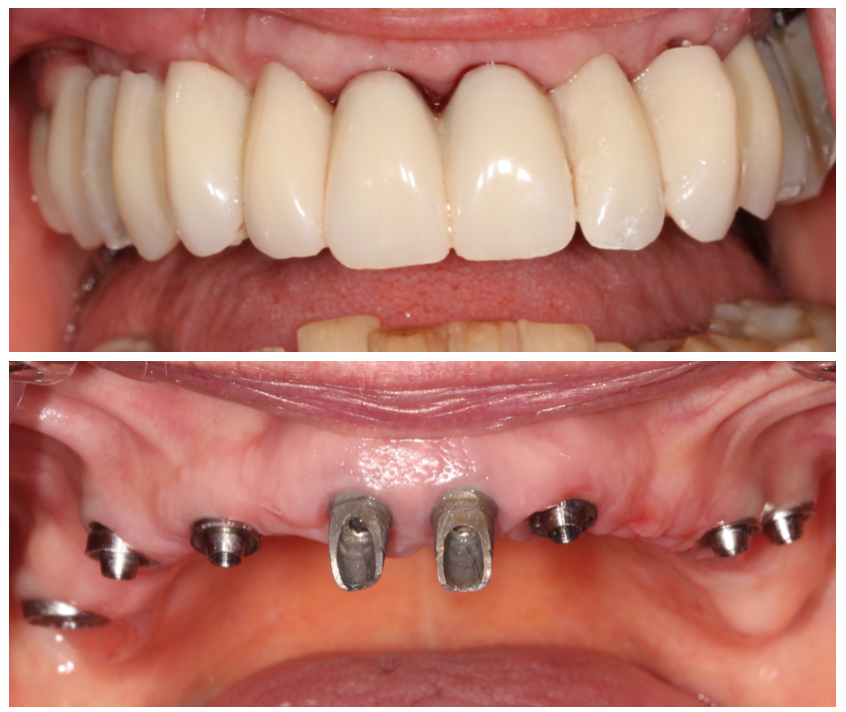

Vues cliniques le lendemain (au moment de la pose du bridge provisoire) :

Bridge provisoire transvissé réalisé au laboratoire :

Ce bridge a été réalisé en technique d’impression numérique avec création de la fausse gencive par maquillage de surface

Bridge provisoire en place avec un rendu esthétique satisfaisant :

Détail de la fausse gencive du bridge provisoire en bouche :